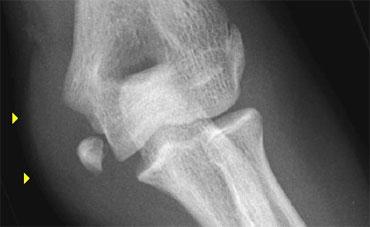

Olecranon fractures

Gãy mỏm khuỷu ở trẻ em ít phổ biến hơn so với người lớn. Như đã đề cập ở trên, chúng thường liên quan đến gãy cổ xương quay và trật khớp xương quay.

Gãy mỏm khuỷu (2)

Không nhầm lẫn điểm bám gân hoặc các trung tâm cốt hóa riêng biệt của nó với gãy xương.

Điểm bám gân có bờ gợn sóng, xơ cứng nhẹ.

Sụn tăng trưởng thường có hướng chếch khác so với đường gãy.

Gãy mỏm khuỷu (3)

Bên trái là một số ví dụ về gãy mỏm khuỷu.

Lưu ý một số trường hợp gãy xương này rất khó nhận thấy.